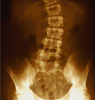

Σκολίωση: Μια «παρέκκλιση» της σπονδυλικής στήλης

Η σκολίωση αρχικά εμφανίζεται σε κάποιο στάδιο της παιδικής ηλικίας δημιουργώντας ανησυχία στους γονείς αλλά και στο παιδί που καλείται να υποστεί τις αισθητικές και λειτουργικές επιπτώσεις της παραμόρφωσης. Αυτό όμως μπορεί να προληφθεί και να αντιμετωπιστεί επιτυχώς αν η σκολίωση διαγνωστεί έγκαιρα, όπως μας εξηγεί ο Δρ Ιωάννης Βαλαβάνης, Ορθοπαιδικός- Χειρουργός Σπονδυλικής Στήλης.

Σκολίωση είναι η τρισδιάσταση παραμόρφωση της σπονδυλικής στήλης, όπου η εμφανίζεται όταν μεν κοιτάμε από πλάγια, με τάση λορδωτική, όταν δε κοιτάμε από μπροστά κυρτωμένη προς τα δεξιά ή αριστερά σχηματίζοντας C ή S.Η στροφή αυτή , παρασύρει και τις πλευρές, σχηματίζοντας το χαρακτηριστικό σκολιωτικό ήβο. Η παραμόρφωση είναι γνωστή από τους χρόνους του Ιπποκράτη, ο οποίος πρώτος χρησιμοποίησε τους όρους κύφωση, λόρδωση, σκολίωση. Διαβάστε στο άρθρο του Παν Σουκάκου, Επ. Καθηγητή Ορθοπεδικής και διευθυντή του Τμήματος Σκολίωσης Σπονδυλικής Στήλης του Ιατρικού Κέντρου Αθηνών για αυτό το συχνό πρόβλημα που ταλαιπωρεί πολλά παιδιά και στην πατρίδα μας.